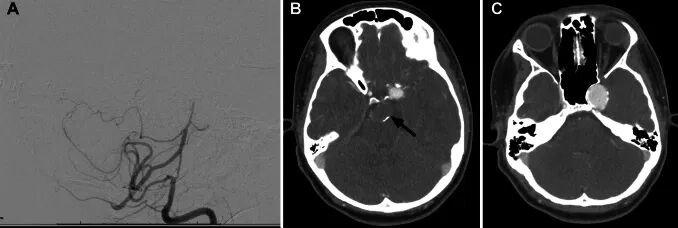

本次影像学检查揭示了病因:小佳左侧颈内动脉海绵窦段存在一个16.9 × 25.9 × 20.5 mm的巨大动脉瘤,伴有蝶骨重塑。进一步仔细阅片发现,基底动脉顶端还存在另一个巨大的双叶型动脉瘤,瘤内可见附壁血栓。

Couldwell教授建议小佳首先接受椎基底动脉球囊闭塞试验。数字减影血管造影显示,基底动脉顶端通畅部分及左侧P1段狭窄处发生了部分重塑。几天后,小佳接受了左枕部开颅手术。在完成颅外-颅内旁路移植术后,Couldwell教授又为其施行了硬脑膜-软脑膜血管融合术,旨在重建左侧大脑后动脉区域血供,并降低对椎基底动脉循环的依赖。

手术过程顺利,术后小佳继续服用阿司匹林。三个月后复查影像显示,基底动脉顶端动脉瘤已完全闭塞并形成血栓,至左侧大脑后动脉区域的颅外-颅内旁路保持通畅。

为处理左侧颈内动脉海绵窦段的另一个动脉瘤,六个月后小佳再次接受数字减影血管造影检查,并接受了Pipeline血流导向装置置入及左侧颈内动脉巨大动脉瘤弹簧圈栓塞术。至此,小佳的两个动脉瘤均完全消失,术后恢复良好,未出现任何并发症或神经功能缺损。